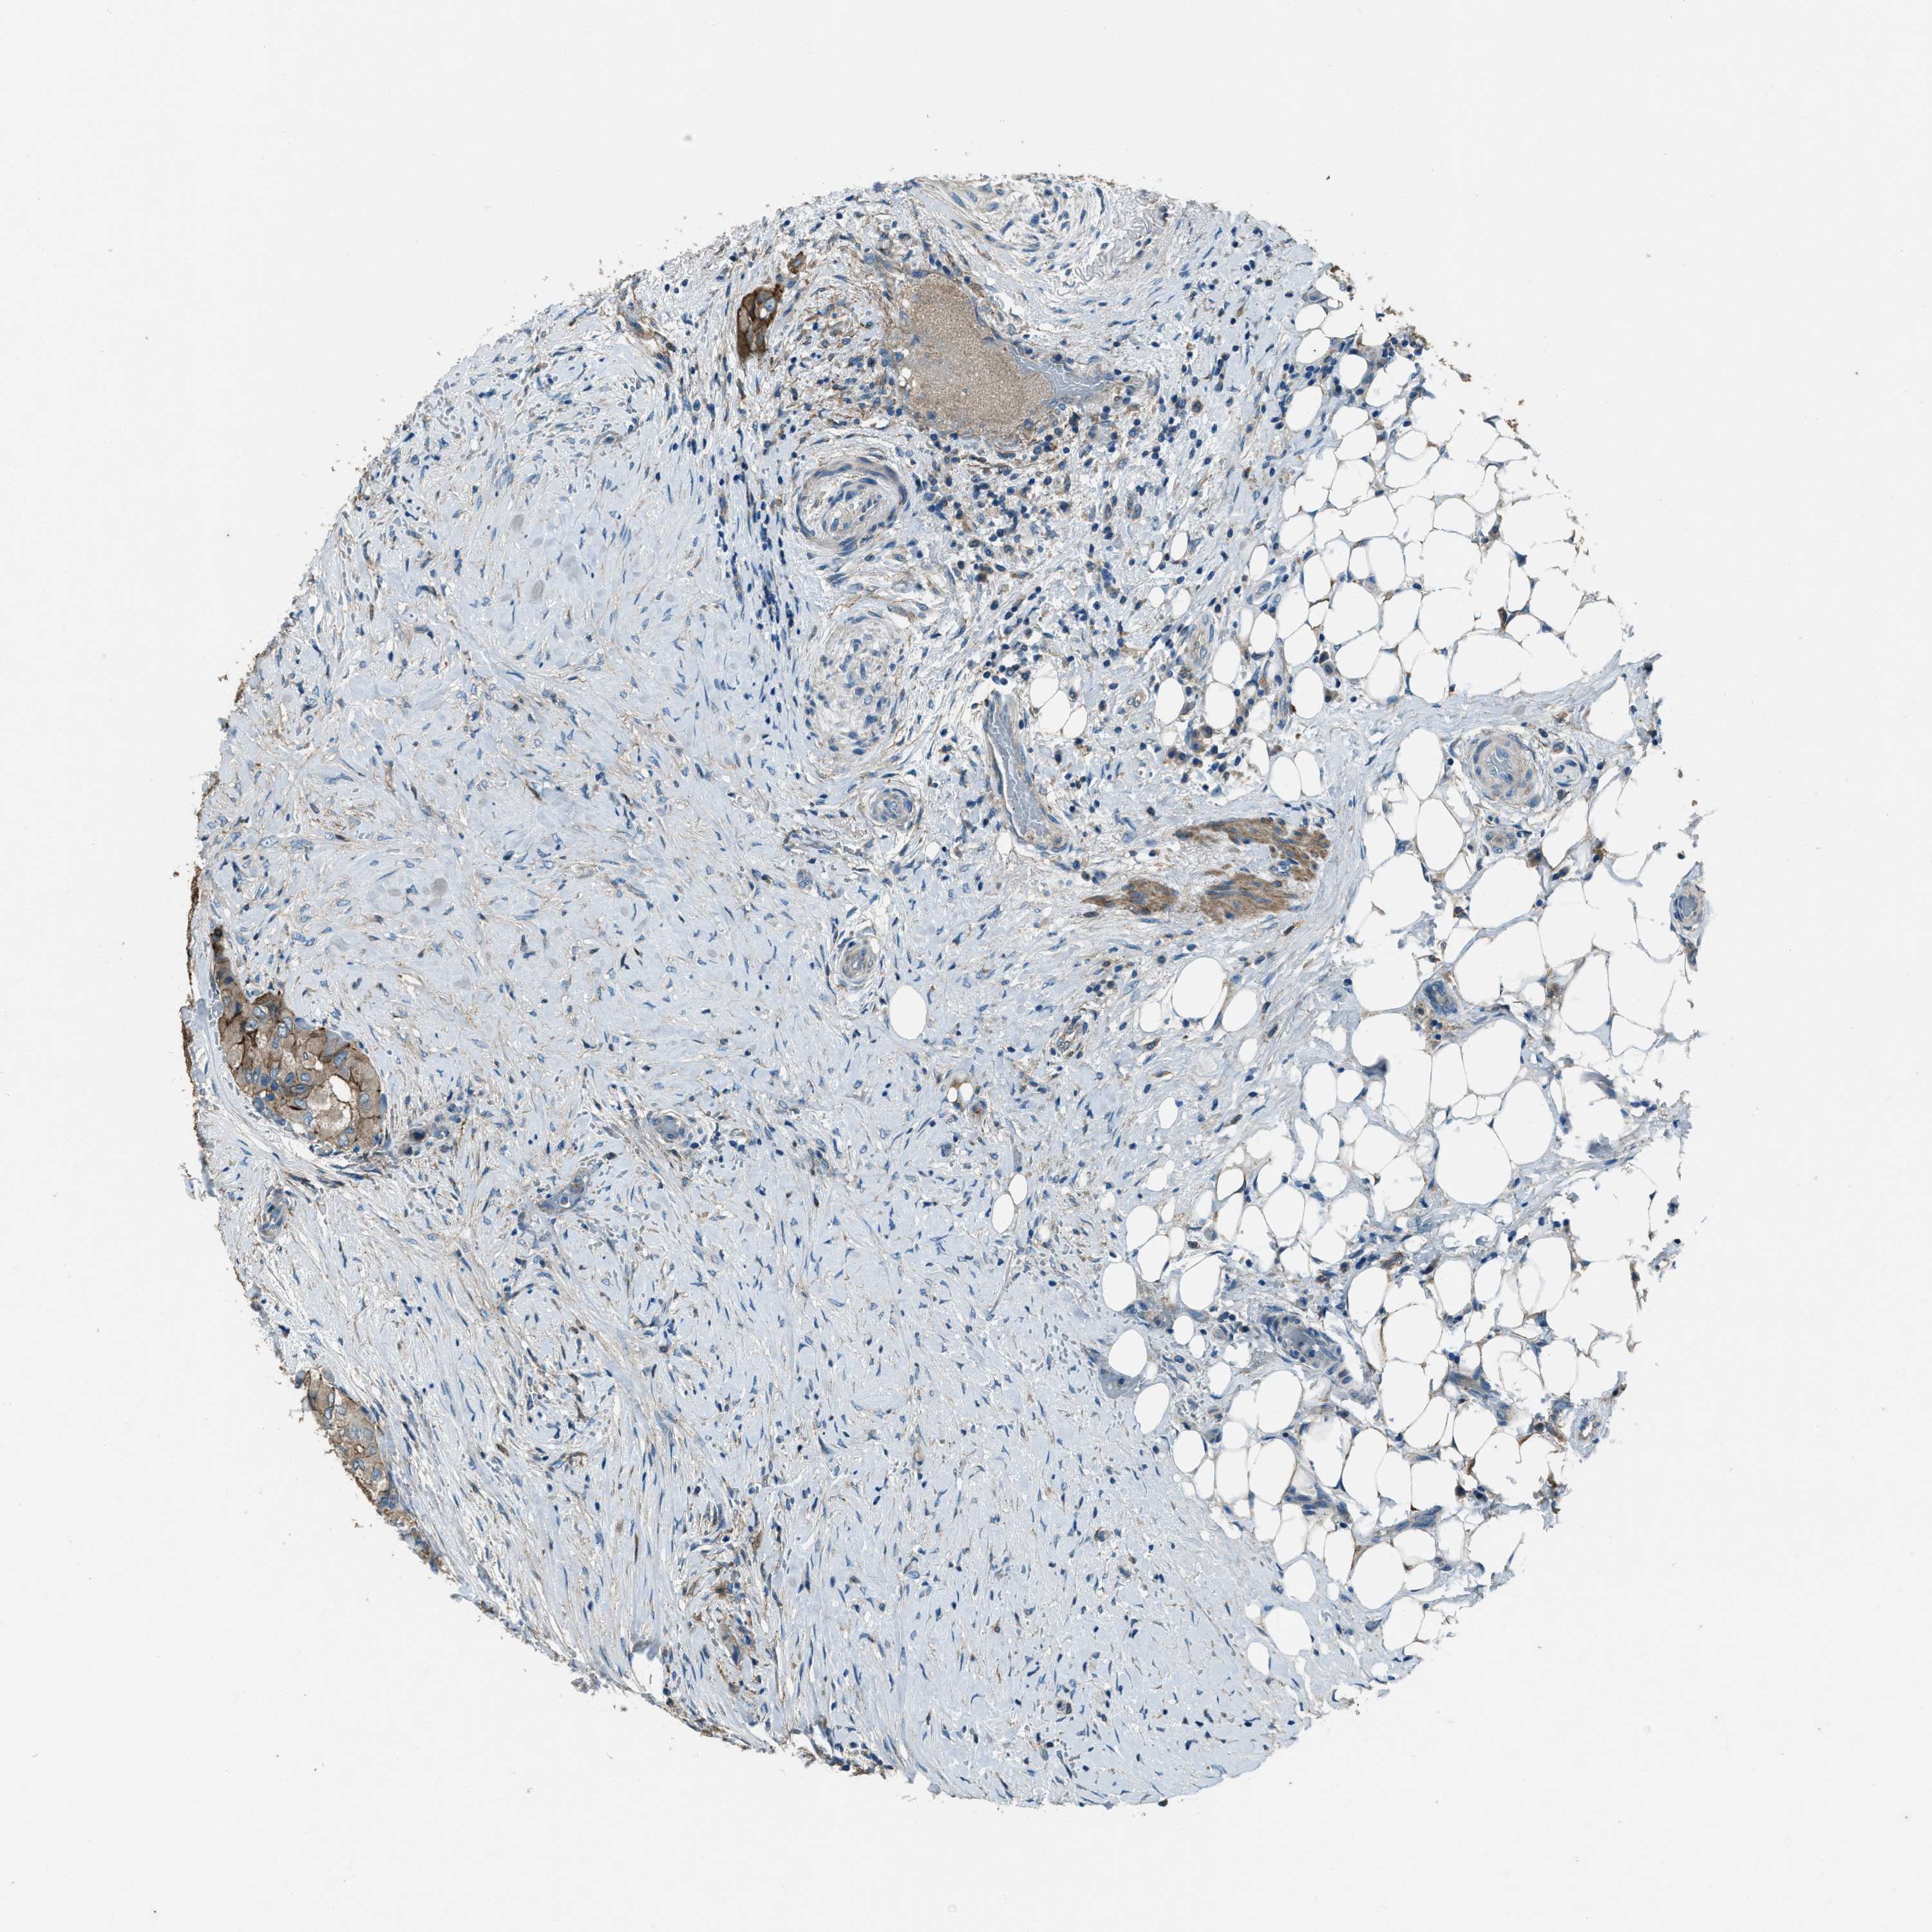

THYROID CANCER - Protein expressioni

A mouse-over function shows sample information and annotation data. Click on an image to view it in a full screen mode. Samples can be filtered based on level of antibody staining by selecting one or several of the following categories: high, medium, low and not detected. The assay and annotation is described here.

Note that samples used for immunohistochemistry by the Human Protein Atlas do not correspond to samples in the TCGA dataset.

Antibody stainingi

Antibody staining in the annotated cell types in the current human tissue is reported as not detected, low, medium, or high, based on conventional immunohistochemistry profiling in selected tissues. This score is based on the combination of the staining intensity and fraction of stained cells.

Each image is clickable and will lead to virtual microscopy that enables deeper exploration of all samples and also displays staining intensity scores, fraction scores and subcellular localization as well as patient and tissue information for each sample.

Antibody HPA020095

Antibody HPA020138

Antibody CAB010878

Antibody CAB080402

Staining

High

Medium

Low

Not detected

Intensity

Strong

Moderate

Weak

Negative

Quantity

>75%

75%-25%

<25%

None

Location

Nuclear

Cytoplasmic/membranous

Cytoplasmic/membranous,nuclear

Papillary adenocarcinoma, NOS

Follicular adenoma carcinoma, NOS